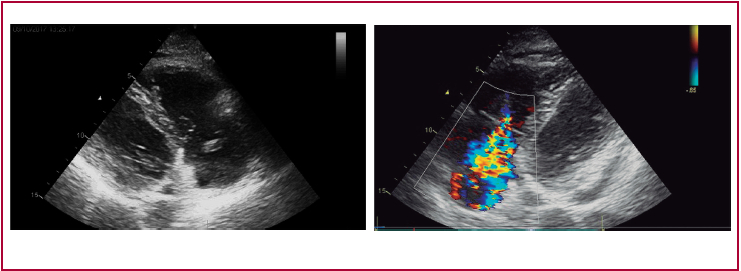

En la analítica presentó elevación de marcadores de necrosis miocárdica y en ECG BRDHH, por lo que a las 48 h se realizó un nuevo ecocardiograma para descartar complicaciones secundarias a la contusión miocárdica; en este se observó la válvula tricúspide con rotura del músculo papilar y eversión del velo anterior, lo que produce insuficiencia tricuspídea (IT) masiva (opacifica toda la aurícula derecha; el flujo Doppler triangular no permite estimar la presión pulmonar; inversión sistólica del flujo en las venas suprahepáticas, movimiento paradójico del septo en relación con sobrecarga de volumen), cavidades derechas ligeramente dilatadas con función sistólica VD conservada y derrame pericárdico ligero.